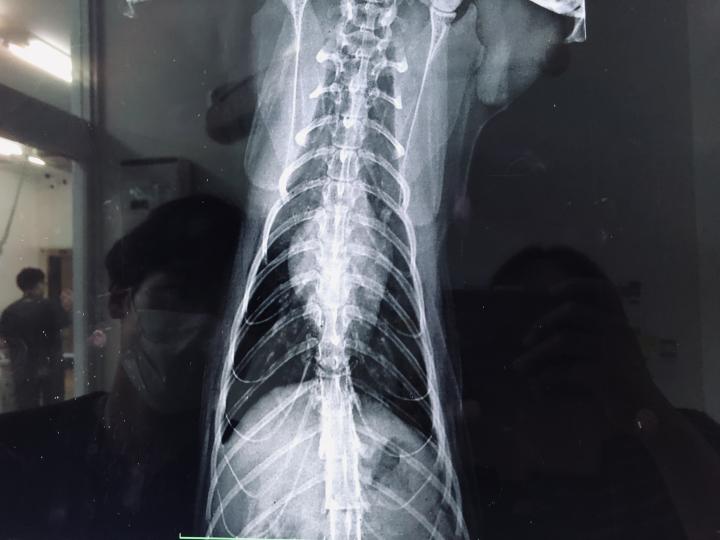

この先、レントゲンの画像あり

ご不快な方はここで🙇

ひなのレントゲン覚え

肺、胃共に問題なし